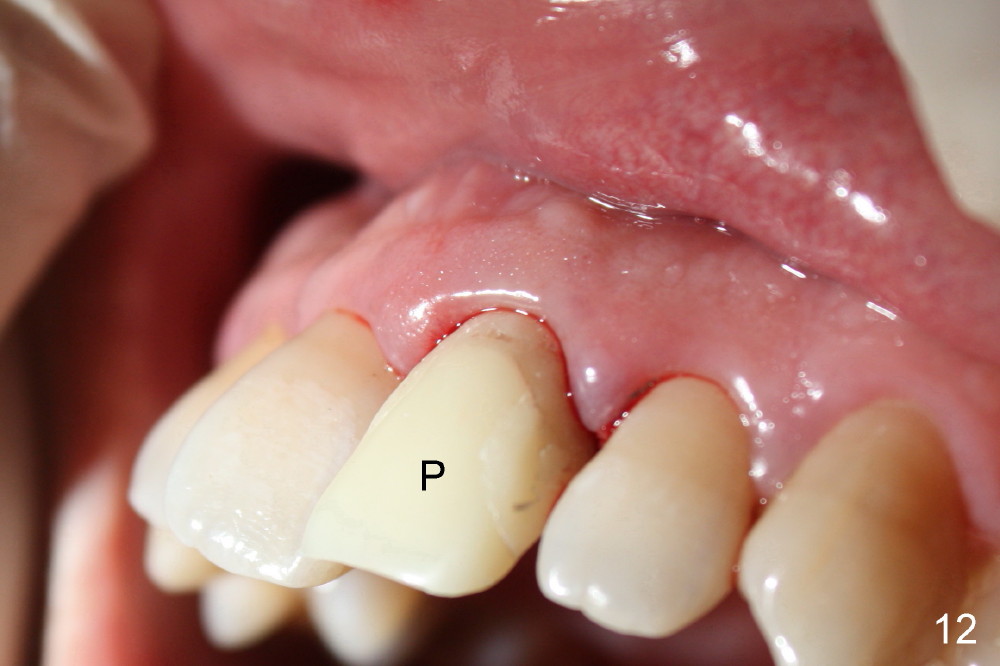

Bone expansion allows the implant (Fig.9 I) to have primary stability (insertion torque between 50 and 60 Ncm), since the cortex of the incisive canal is apparently intact.  Allograft is placed in the labial gap (Fig.10, 11 *) following installation of the abutment (A).  Finally an immediate provisional (Fig.10,12 P) is cemented.  Fig.13,14 are taken 8 days postop.  The patient returns 3 months postop (Fig.15,16).  Osteointegration appears to have occurred (Fig.15 arrowheads) and is more obvious 9 months postop (Fig.17).